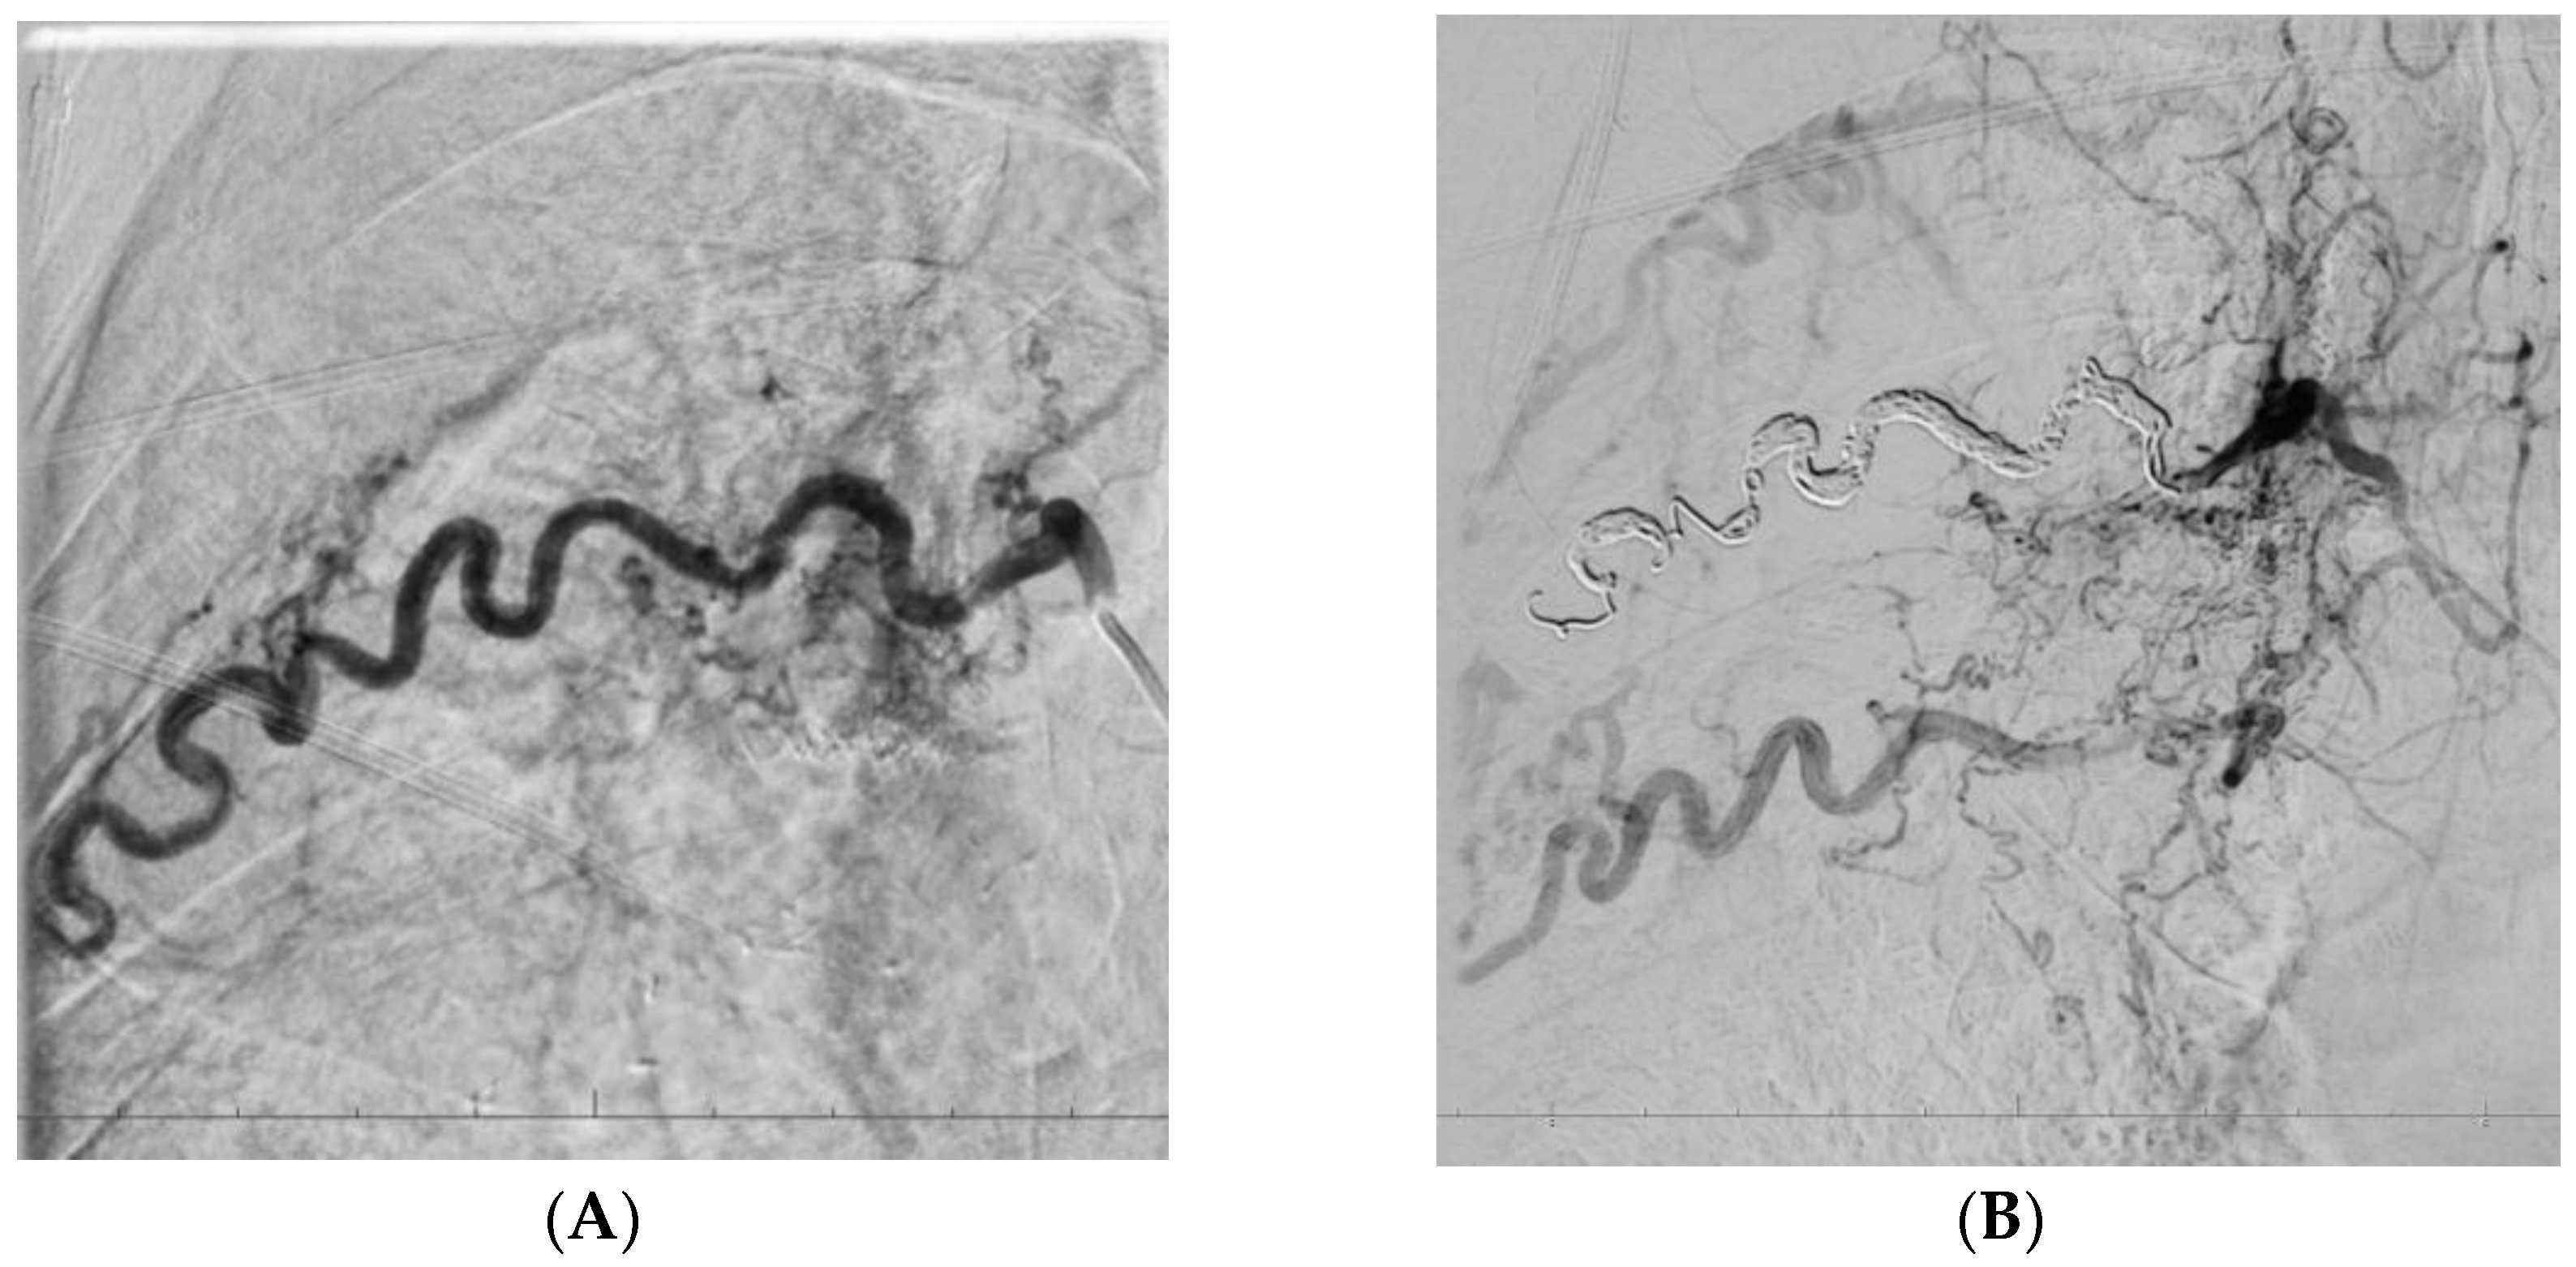

| P08 | Dilated multiple R BA (one from arch, two from descending aorta) (up to 3.2–3.6 mm) CT signs of fistulas/anastomoses in RUL Apical pleural thickening bilaterally | R BA | Yes |

| R&L intercostal aa. | Yes | ||